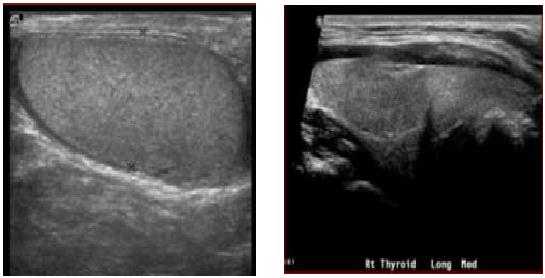

В норме яичко определяется как гомогенная структура овальной формы, эхогенность которой сравнима с эхогенностью щитовидной железы.

На первой картинке визуализируется гомогенная структура яичка в продольной плоскости. Текстура яичка такая же, как у щитовидной железы, представленной на втором изображении.

На первом изображении видна головка придатка яичка. По сравнению с яичком придаток изоэхогенный или чуть более эхогенный.